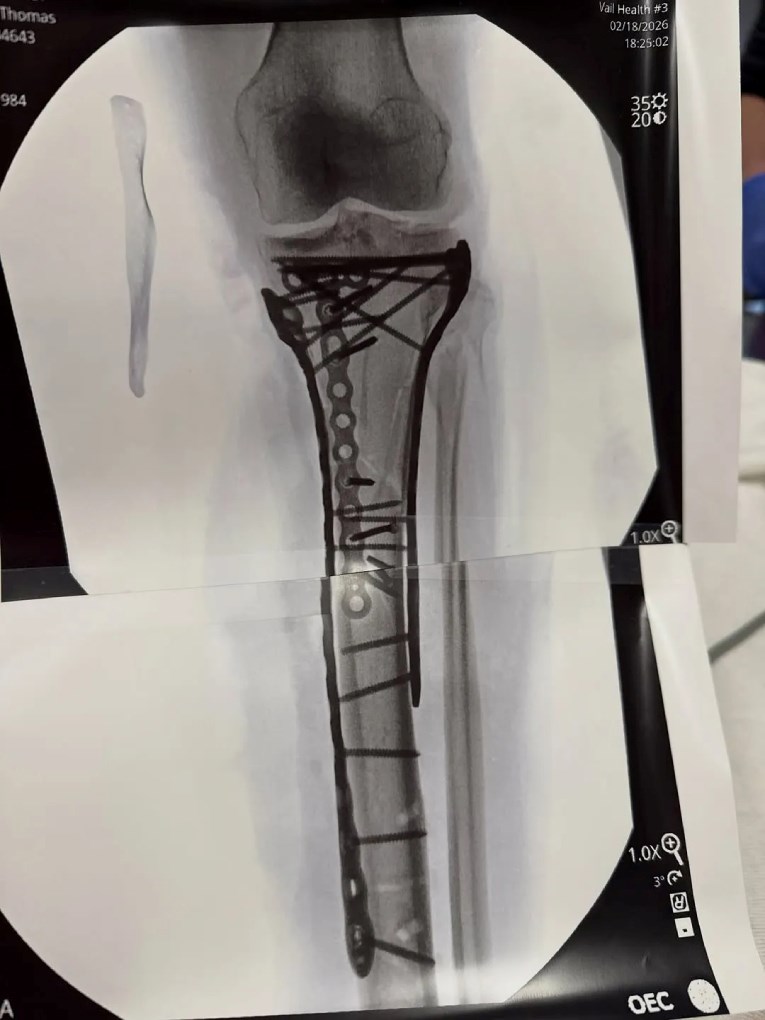

„Како што можете да видите, беа потребни многу плочи и завртки за да се состави сè повторно, но д-р Хакет направи неверојатна работа. Со оглед на сериозноста на повредата, закрепнувањето од операцијата е малку потешко и сè уште не сум излегла од болница… Но, блиску сум. Чекор по чекор. Наскоро ќе навлезам во повеќе детали за повредата и што значи сето тоа.“

Заедно со објавата, таа прикачи две рендгенски снимки на кои се гледаат најмалку 20 плочки и завртки вградени во нејзината нога. Таа исто така сподели видео снимено на пат кон операционата сала и фотографија од неа како одмара во болнички кревет.